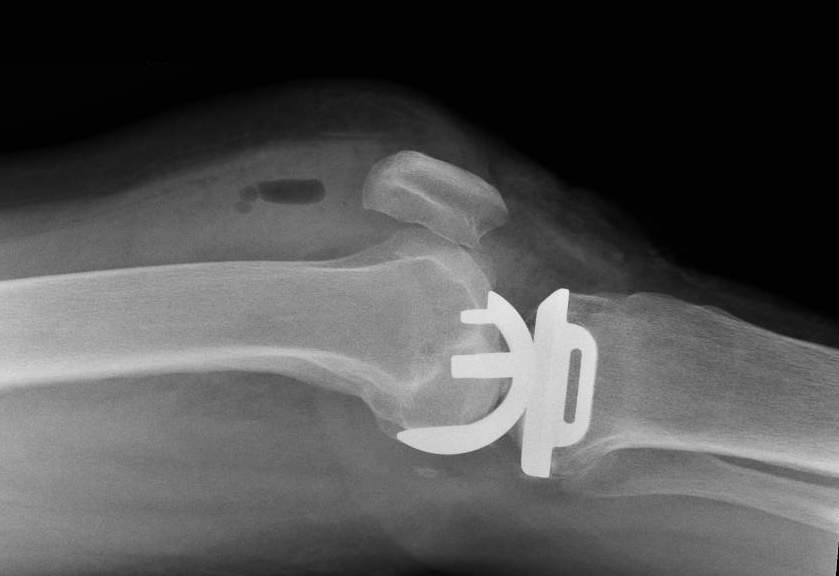

Often only one compartment (medial, lateral, patella) of the knee wears out and the remaining cartilage and ligaments in the other compartments are preserved and in a good condition. In this situation a partial (unicompartmental) knee replacement is indicated.

Through a minimally invasive incision the inner compartment of the knee is replaced with a mobile bearing prosthesis. This consists of a metal femoral and tibial component with a polyethelene (plastic) insert that moves as the knee bends. The cruciate ligaments are preserved so the knee will feel ‘more normal’ thus providing improved functional results following surgery.